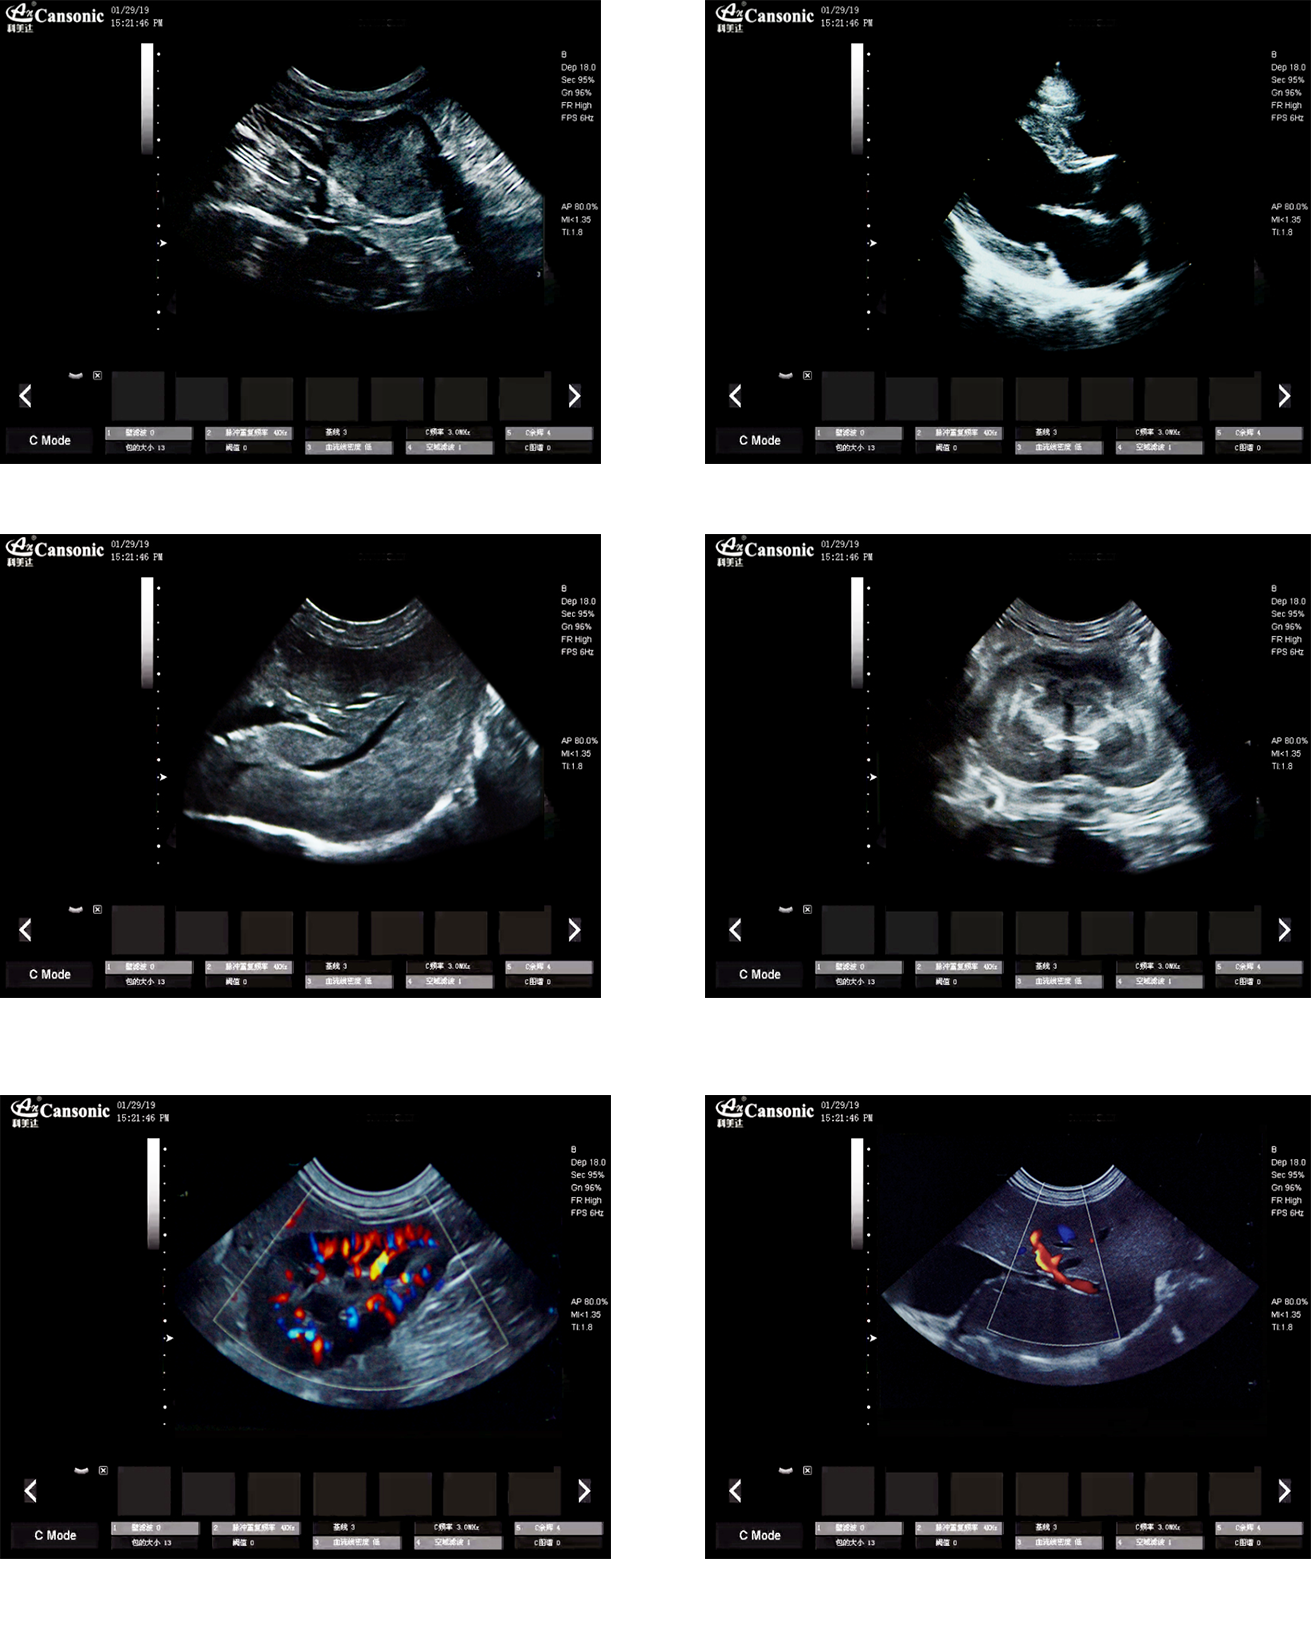

1、薈萃高端彩超的專業(yè)技術,各類型的專業(yè)獸用探頭,提供完整的動物臨床診療方案

2、專業(yè)的獸用彩超軟件,適合犬、貓、馬、牛、羊等各類大小動物彩超檢查

3、完備的獸用高端功能,能量多普勒POWER模式彩色多普勒Color成像模式

臨床圖示